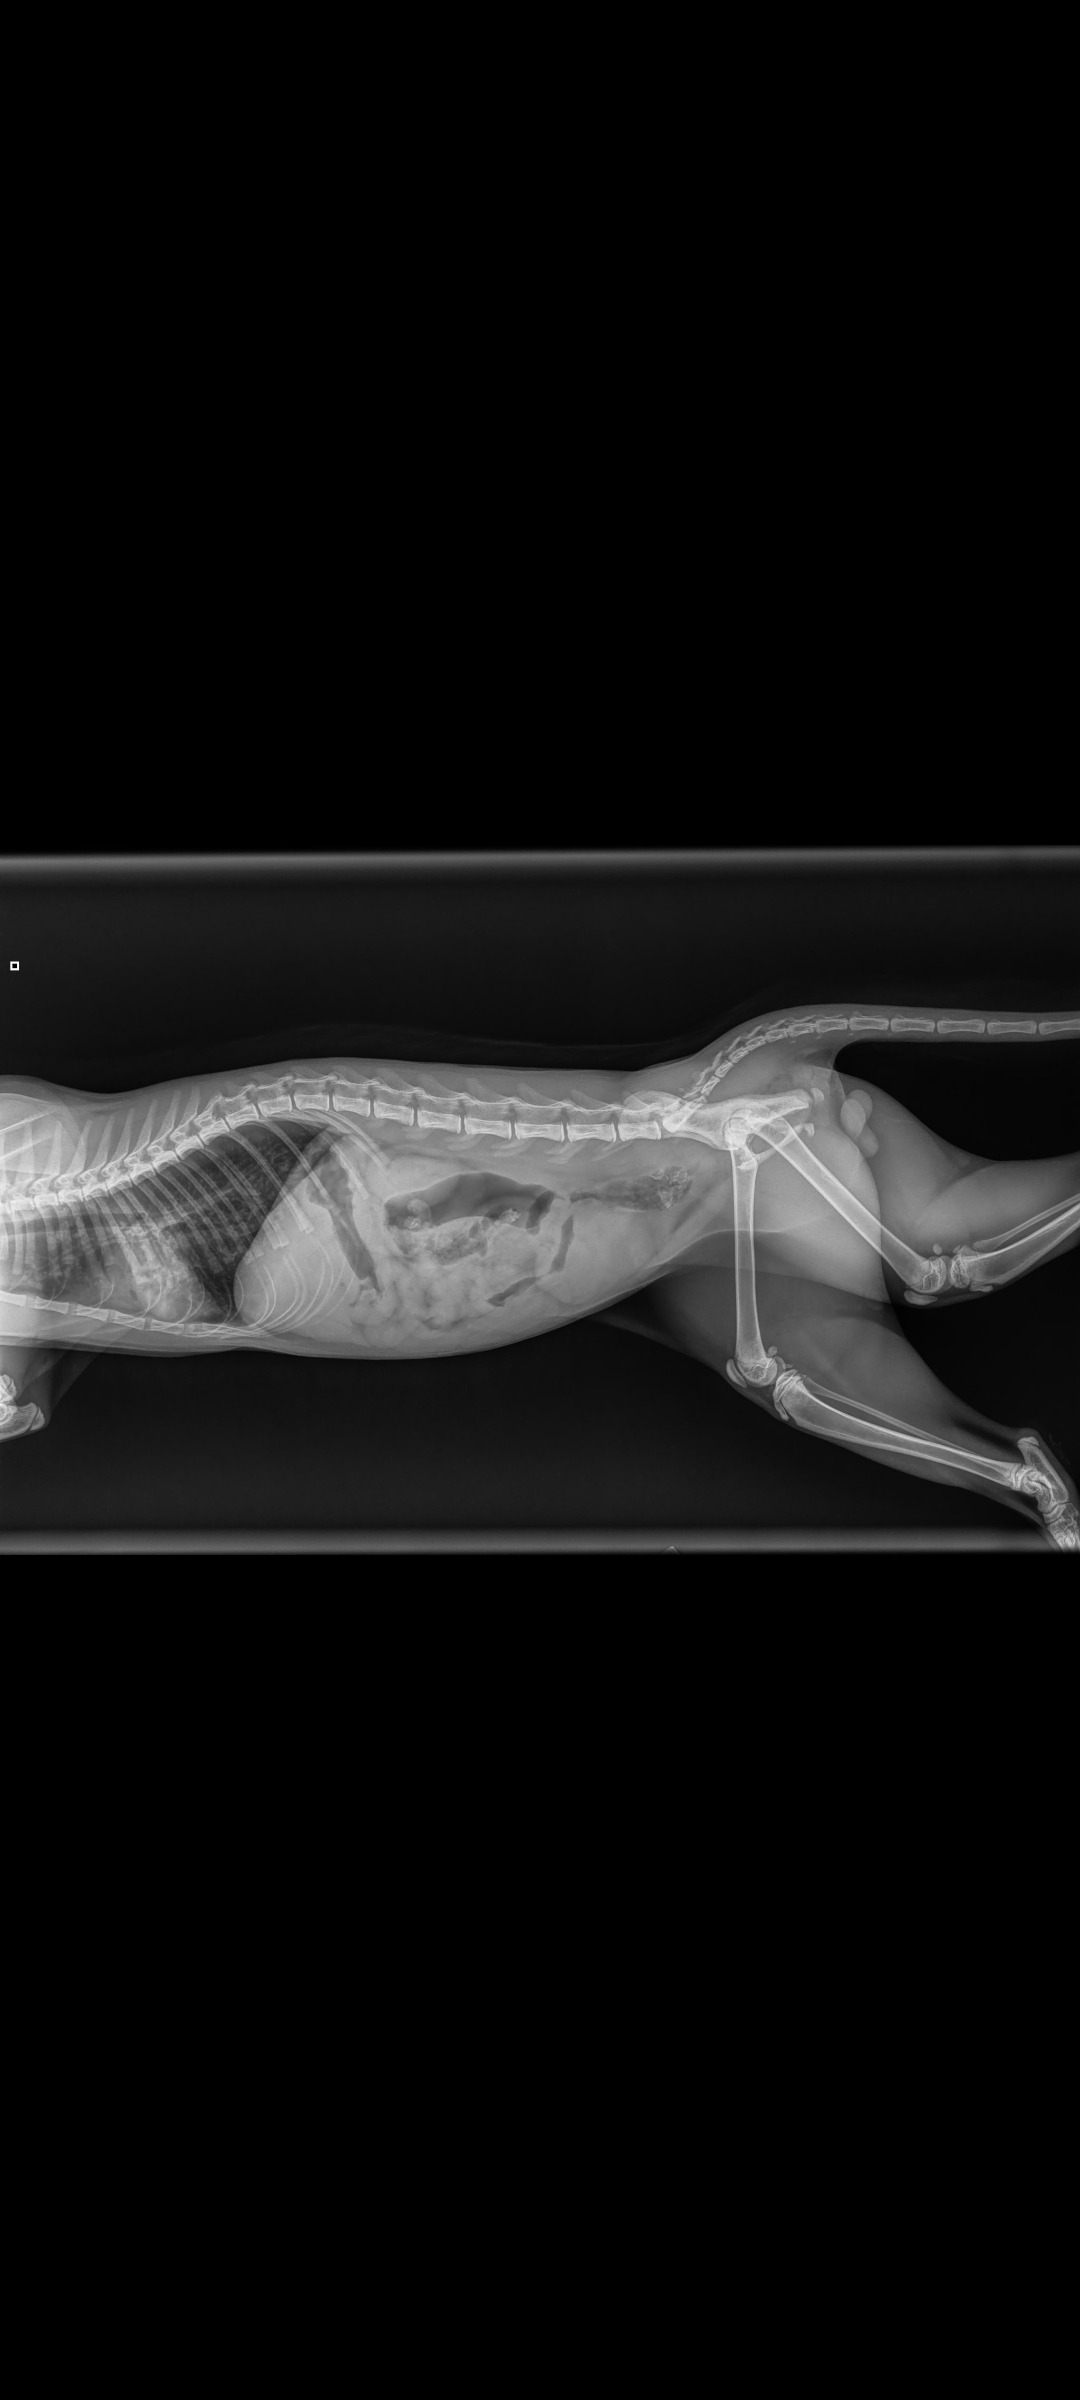

He has pretty banged up and bruised lungs, which is a huge concern. He has to be closely monitored to watch that the blood pockets in his lungs don't pop, which means more scans.

He also has a fractured/broken pelvis. He is unable to walk. He is crate/cage bound for 2 weeks to minimize any movement in hopes that it heals properly but will also require physical therapy and more scans and x-rays.